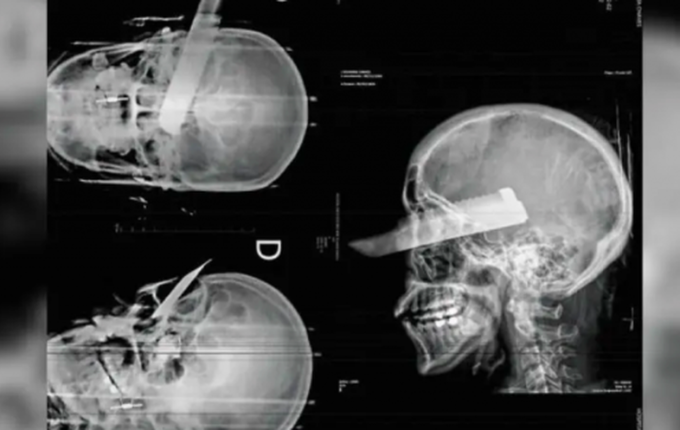

Uma mulher sofreu uma tentativa de feminicídio na manhã desta segunda-feira, 2, em São Carlos, ao ser atacada pelo companheiro dentro da residência do casal. O agressor desferiu um golpe de faca no rosto da vítima, atingindo o olho direito, mas o crime não se consumou, segundo a polícia, graças ao pronto atendimento médico.

Conforme apurado pela Polícia Civil, o suspeito agiu com a intenção de a matar. A vítima conseguiu escapar parcialmente da agressão, mas foi atingida enquanto tentava fugir. Ela recebeu atendimento de emergência e passa por acompanhamento médico.